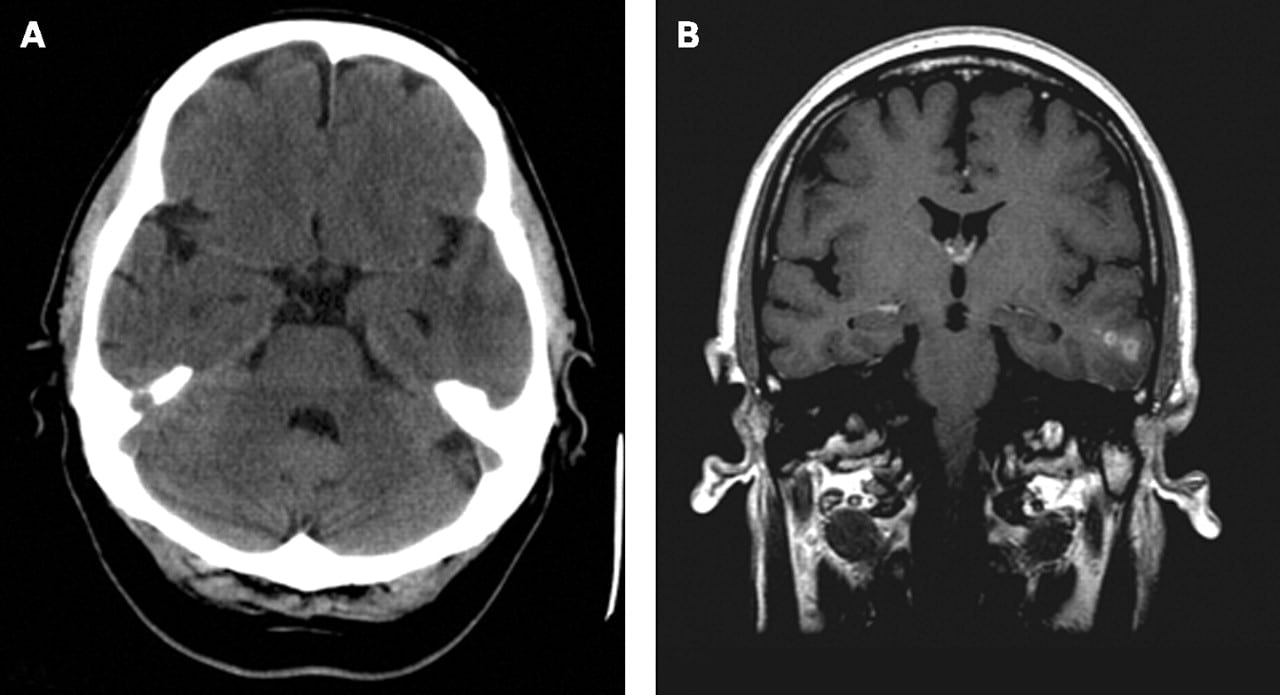

胶质母细胞瘤体积常较大,多起源于脑白质中,侵犯较大范围。大脑的前半部是好发部位,特别常见于额叶,颞叶次之,枕叶少见。肿瘤常侵犯几个脑叶。深部结构(特别是胼胝体)常被侵犯并成为肿瘤跨越中线的桥梁。当额、顶、枕叶的胶母细胞瘤经胼胝体侵犯及对侧大脑半球时,在冠状切面内肿瘤具有蝴蝶形的分布范围,这是这种肿瘤的特征。颞叶胶母细胞瘤常侵犯基底节。基底节和丘脑的胶母细胞瘤常经中间块侵入对侧丘脑,或经底丘脑和大脑脚侵入中脑。小脑的胶母细胞瘤少见。

影像表现

2、MRI征象:平扫时,表现为信号不均匀、形态不规整、边缘欠清楚的长T1、长T2异常信号影。瘤旁水肿一般比较重,邻近脑室可见明显的受压变形及移位。肿瘤内灶性坏死和出血比较常见,增强扫描肿瘤多呈不规则花环样强化。